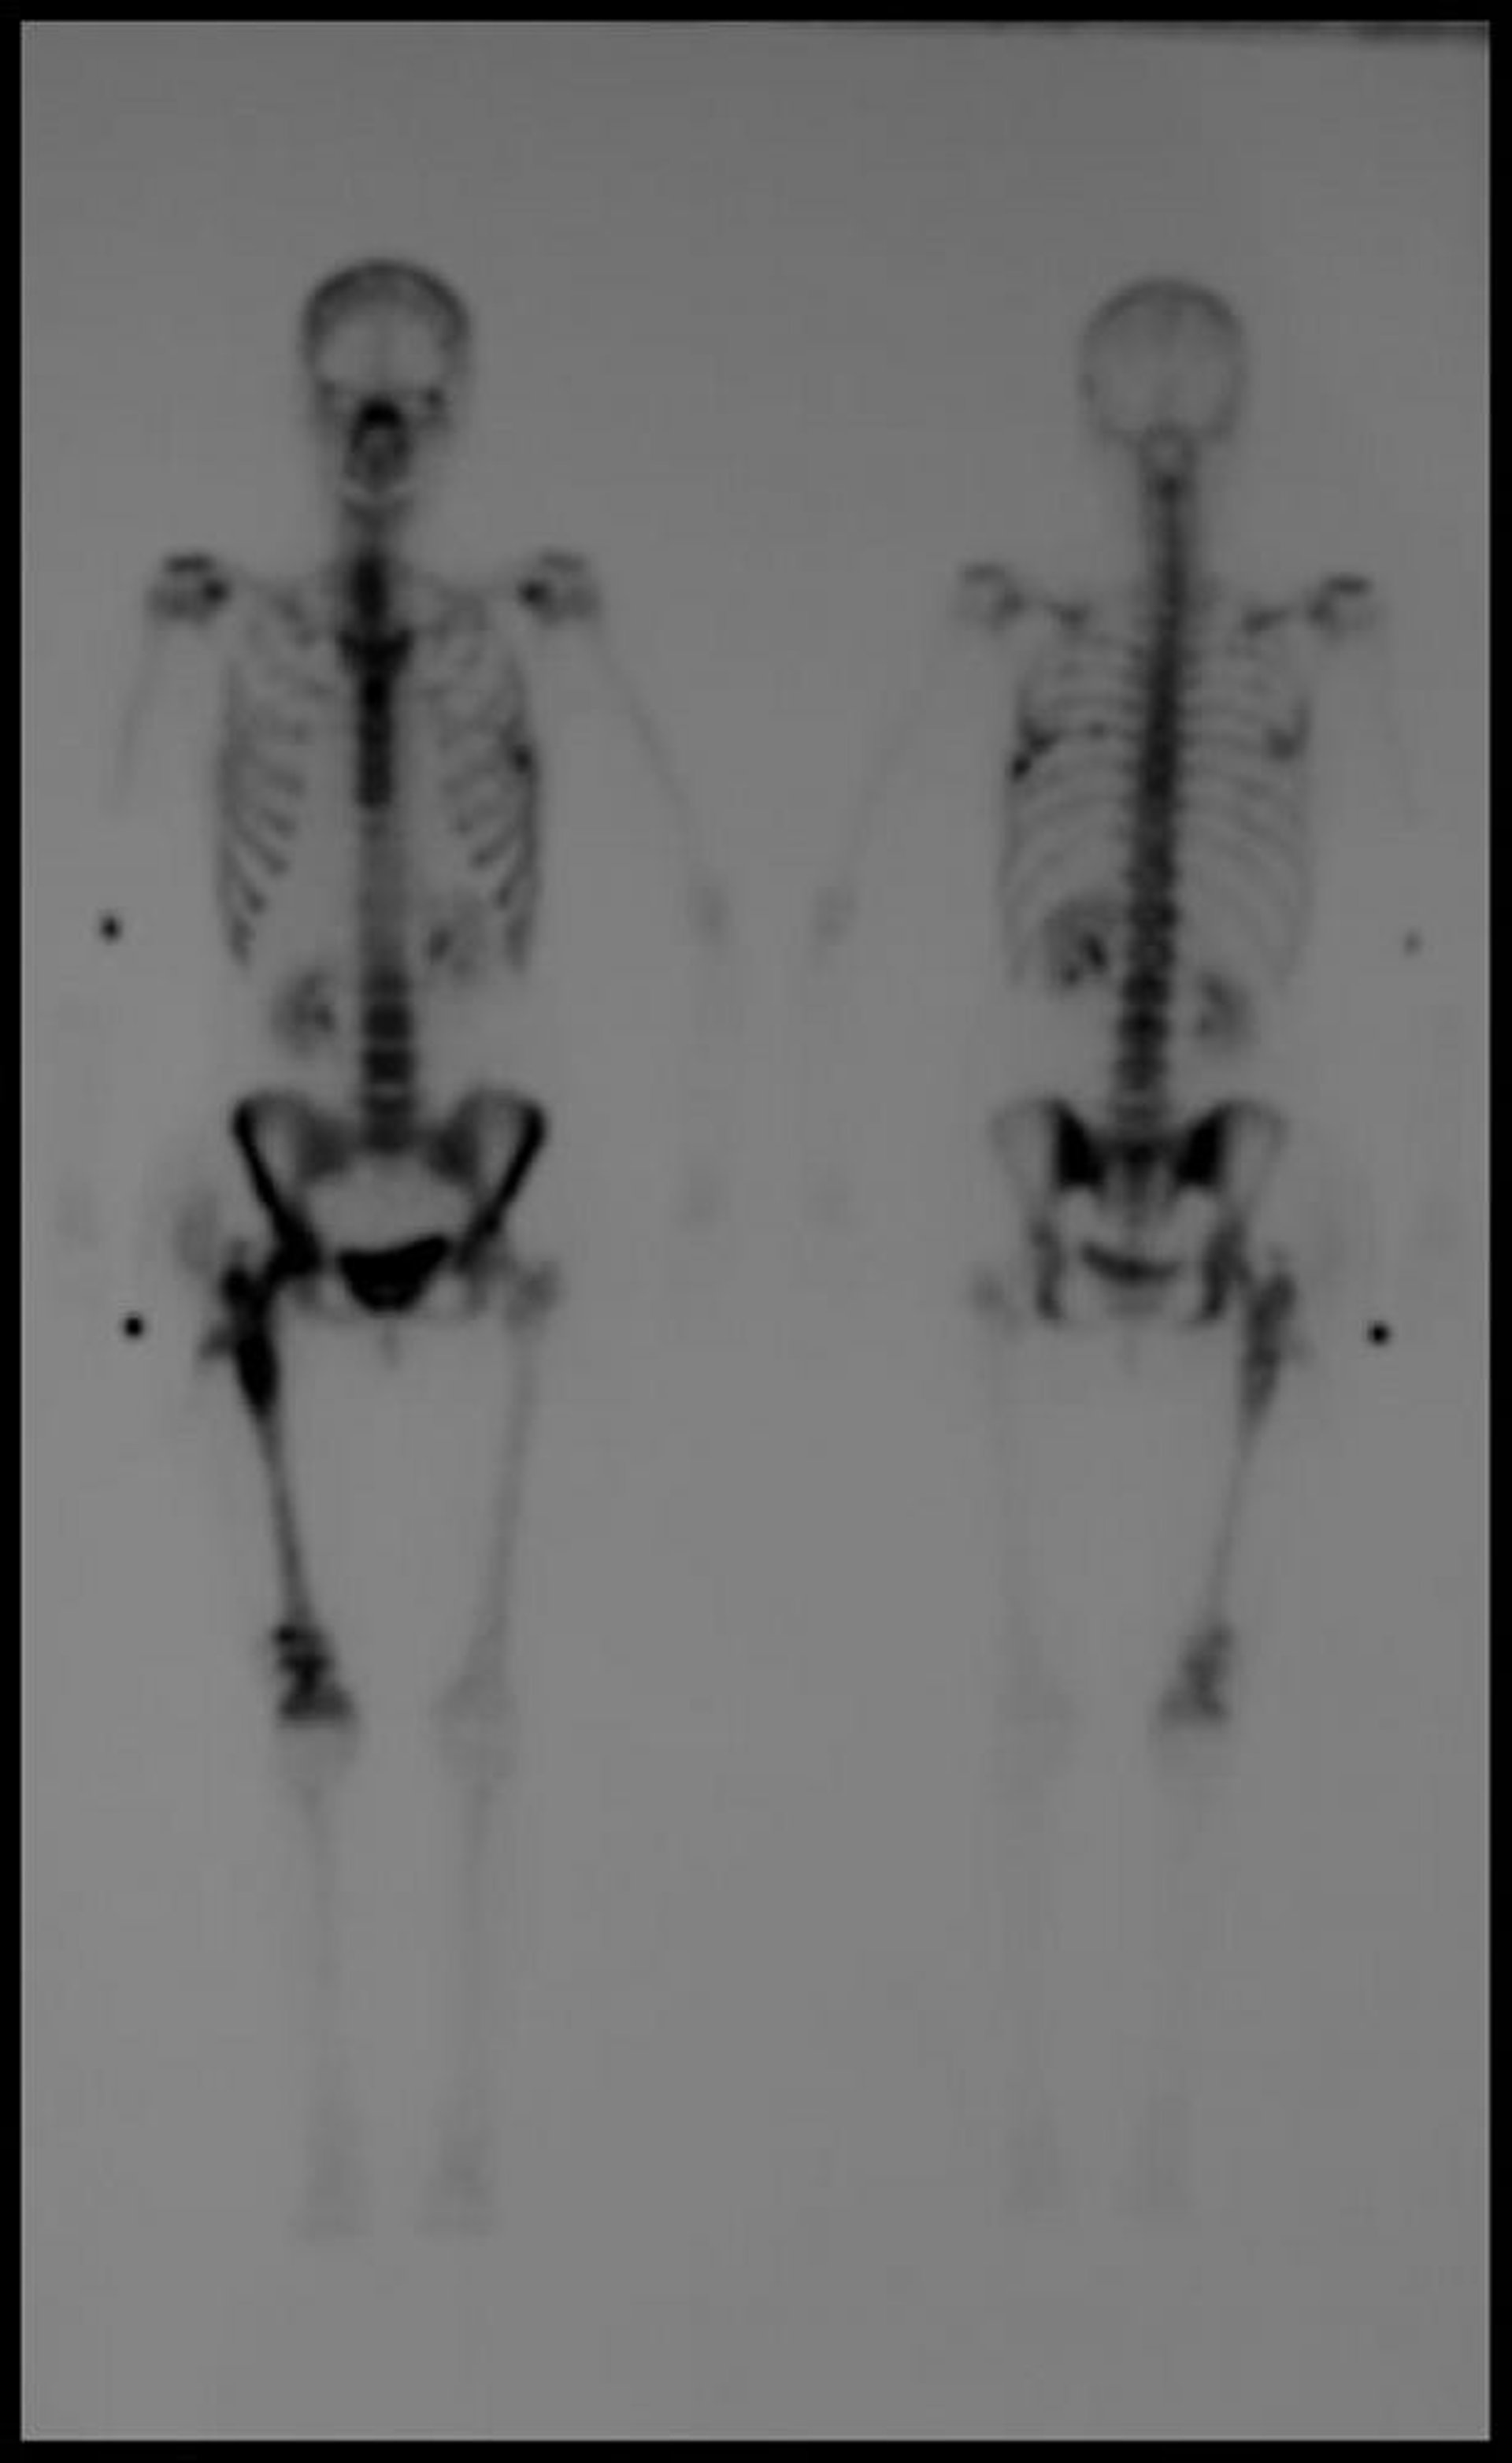

Bone Scintigraphy of the Whole Body

Delayed whole-body technetium-99m bone scintigraphic image shows multiple foci of increased uptake consistent with metastatic disease.

Image courtesy of Hakan Ilaslan, MD.